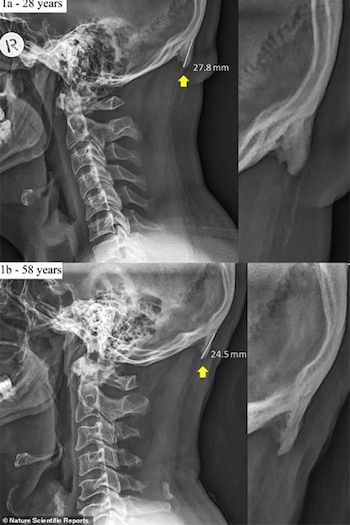

Este tipo de protuberancias occipitales externas se desarrollan en la base del cráneo y el número de personas que lo desarrollan va incrementando.

En los inicios de la década de 1800 no era tan notable esa protuberancia, pero ahora se puede sentir los bultos óseos con los dedos o verlos en personas calvas. Solo que las personas que lo están desarrollando más rápido son los jóvenes.

Las investigaciones mencionan que este tipo de excesos aparecen en jóvenes de 18 a 30 años. Motivo por el cual los científicos de la Universidad de la Costa del Sol en Queensland realizaron una investigación detallada del fenómeno.

Los científicos escanearon más de mil cráneos de personas de 18 a 86 años, según mencionó el medio BBC Future.